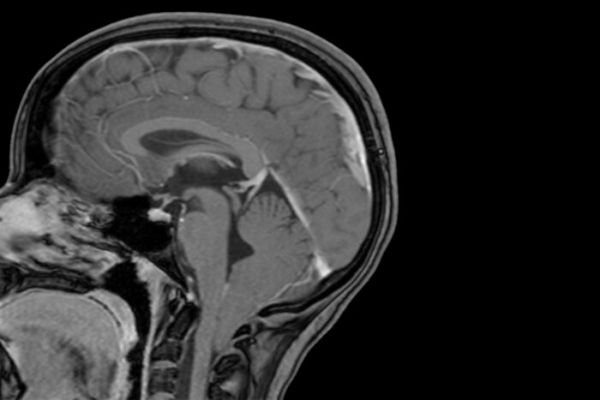

The condition occurs when the lowest parts of the brain are found below the base of the skull. The study also revealed that children with unusually large heads are four times more likely to be diagnosed with Chiari 1 malformation than their peers with normal head circumference.

Image: The lowest part of a child's brain is visible below the bottom of the skull in this MRI scan and shows evidence of a Chiari 1 malformation. Researchers at Washington University School of Medicine in St. Louis have shown that Chiari 1 malformation can be caused by variations in two genes linked to brain development, and that children with large heads are at increased risk of developing the condition.  CREDIT: David Limbrick